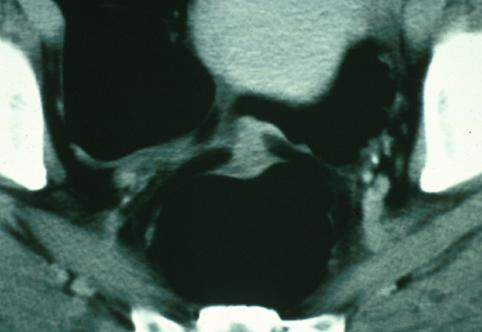

疾病(病理主体)的分类肿瘤样病变/子宫内膜症

部位(按器官分)大肠/乙状结肠

检查方法CT

肿瘤最大直径35~40